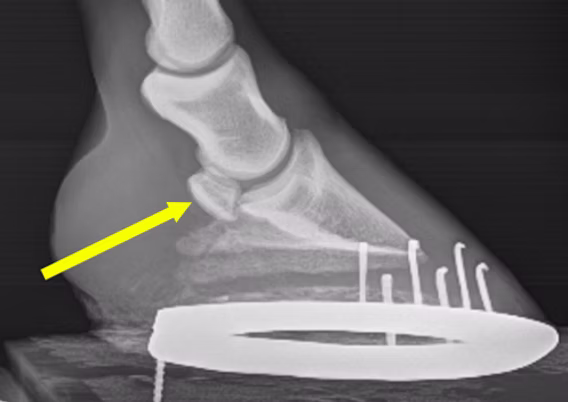

Les examens d’imagerie : radiographies, IRM et échographie

Après l’examen clinique et les tests d’anesthésie, le passage aux examens d’imagerie devient souvent nécessaire pour obtenir une confirmation objective du diagnostic.

La radiographie du pied est l’examen de base. Elle permet de visualiser l’os naviculaire et de rechercher des signes d’arthrose, de remaniements osseux, de kystes, ou de fragments osseux.

Il s’agit d’un outil incontournable pour évaluer l’état structurel du petit os, mais il ne montre que les anomalies avancées.

Cependant, il arrive que des chevaux présentent un syndrome naviculaire douloureux alors que leurs radiographies sont peu modifiées, ou que des lésions radiologiques existent sans douleur. D’où l’intérêt d’associer d’autres modalités d’imagerie si besoin.

syndrome-os-naviculaire-cheval-radio